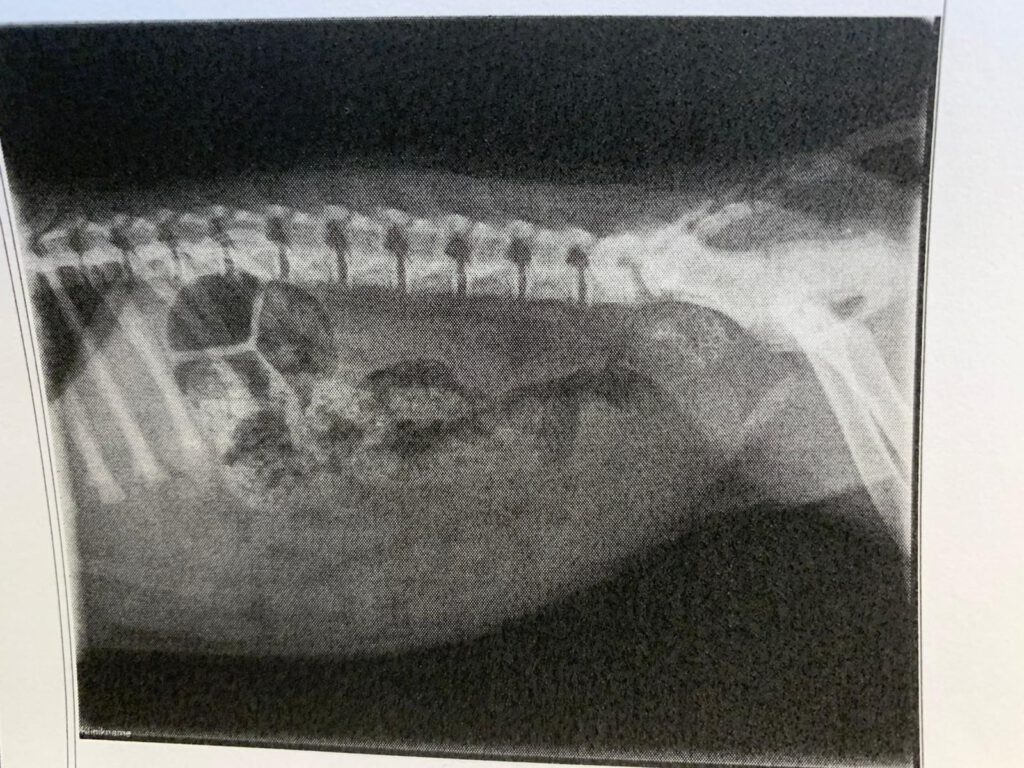

Diese Situation erinnerte mich an eine lange Reise, die wir bereits hinter uns hatten. Als Frieda ein Welpe war, verschluckte sie einmal ein größeres Stück Knochen, das den Magenausgang blockierte. Sie konnte nichts mehr verdauen und erbrach sich nach jeder Mahlzeit. Die Tierärztin riet uns, abzuwarten, bis sich der Knochen auflösen würde – danach folgten Monate voller sorgsamer Ernährung, feinster Pürierungen und minutiöser Beobachtung, was sie vertrug und was nicht. Ich dokumentierte alles in einem Tagebuch: Mengen, Konsistenzen, Fütterungszeiten. wie oft übergeben und feierte es, wenn es mal ausblieb…